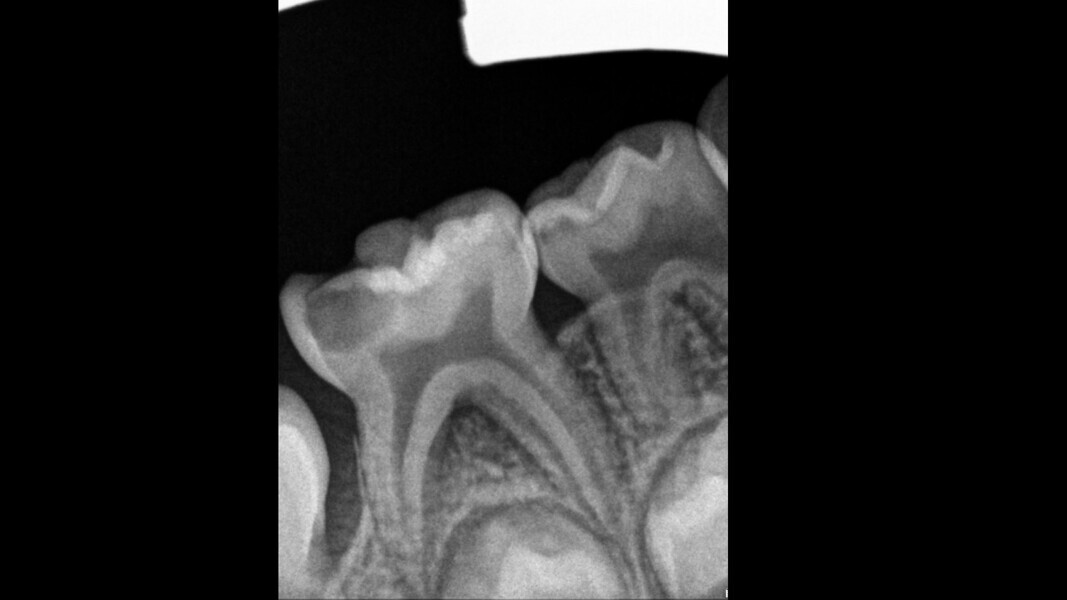

Case 3 (Figs. 10–13)

This male patient was 7 years old and presented with mild pain that had lasted for several days. An extensive and deep cavity in the mandibular left first primary molar was observed. There was no swelling of the gingiva, but the tooth was painful on percussion. The radiograph showed the severity of the decay but no consistent changes to the surrounding bone. Pulpectomy was the treatment of choice. The diagnosis of pulp necrosis was confirmed once the access cavity had been performed, and three canals were located and fully negotiated. At a second appointment, 15 days later, the tooth was totally asymptomatic and the decision was made to restore with a stainless-steel crown. The 36-month control showed the tooth to be in normal function and completely healthy.